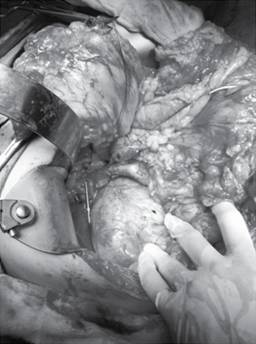

El acceso al estómago es a través de una incisión vertical en la cara anterior a un tamaño suficiente que permita la manipulación y colocación de los puntos de fijación del páncreas. Se coloca el estómago sobre el área pancreática antes de efectuar el corte en la pared posterior, permitiendo determinar el sitio donde se realizará la anastomosis, el corte deberá ser transversal al estómago y la longitud de dos tercios del diámetro del muñón pancreático, lo que permitirá que al momento de introducir el remanente pancreático se ajuste a la pared gástrica asegurando un sello periférico. La sutura que se emplea es monofilamento no absorbible (polipropileno) con aguja atraumática (calibre 0), se colocan puntos en la periferia de la anastomosis por dentro de la cavidad gástrica que abarquen la pared total de estómago y tejido pancreático. El cierre de la incisión gástrica anterior se afronta con sutura absorbible (poliglactina), puntos invaginantes en súrgete (Figura 2). El resto de las anastomosis se lleva a cabo con preservación pilórica como lo describe Traverso,15 cuando no es posible la preservación pilórica puede utilizarse reconstrucción con gastroyeyunoanastomosis latero lateral en Y de Roux.